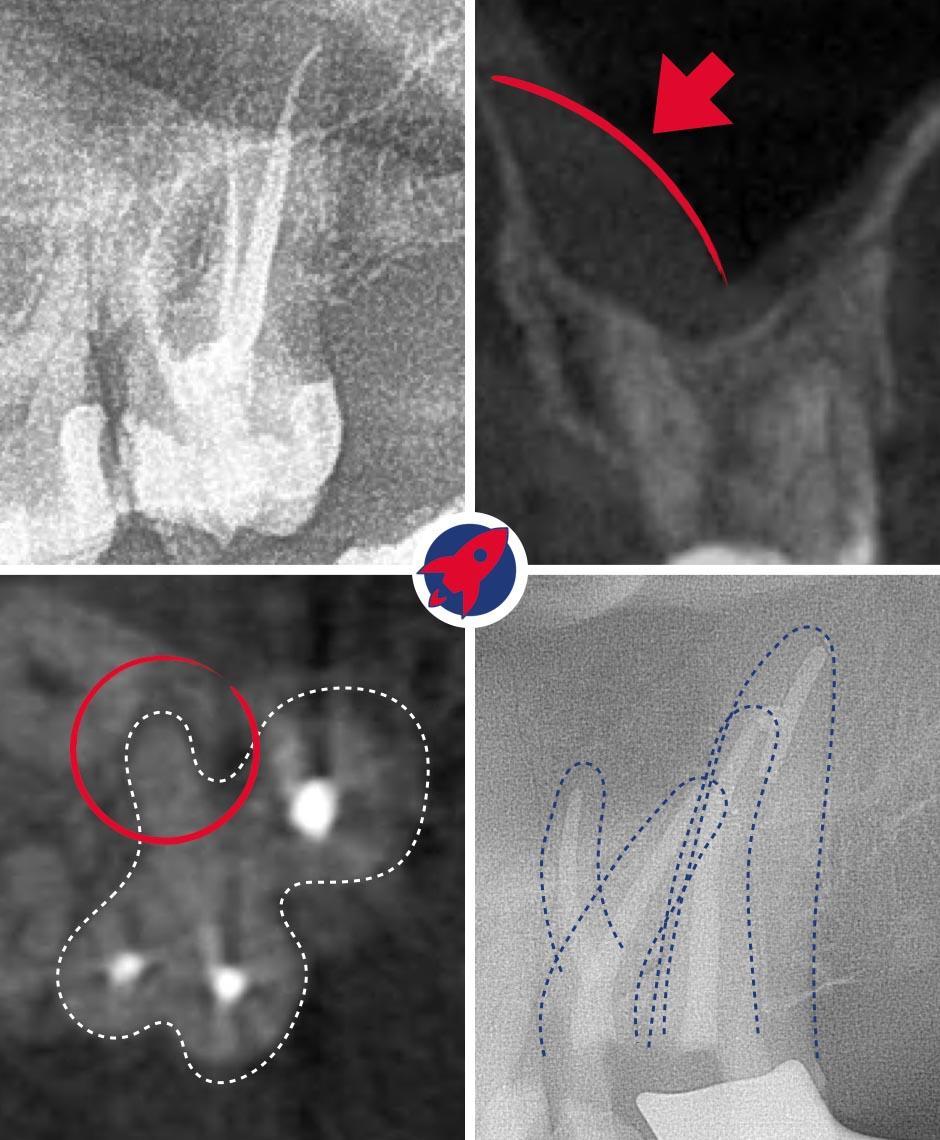

Treatment Under the Dental Microscope

The core of our endodontics. The up to 25x magnification enables the visualization of the finest canals, which are impossible to find with the naked eye.

Gentle Preparation

Instead of manual files, we use flexible, machine-driven nickel-titanium instruments that thoroughly and gently clean even severely curved canals.

Cleaning Under the Microscope

The tooth is isolated. Using the X-ray and the magnification of the microscope, the canals are opened, flushed, and cleaned and disinfected with machine-driven instruments down to the tip.